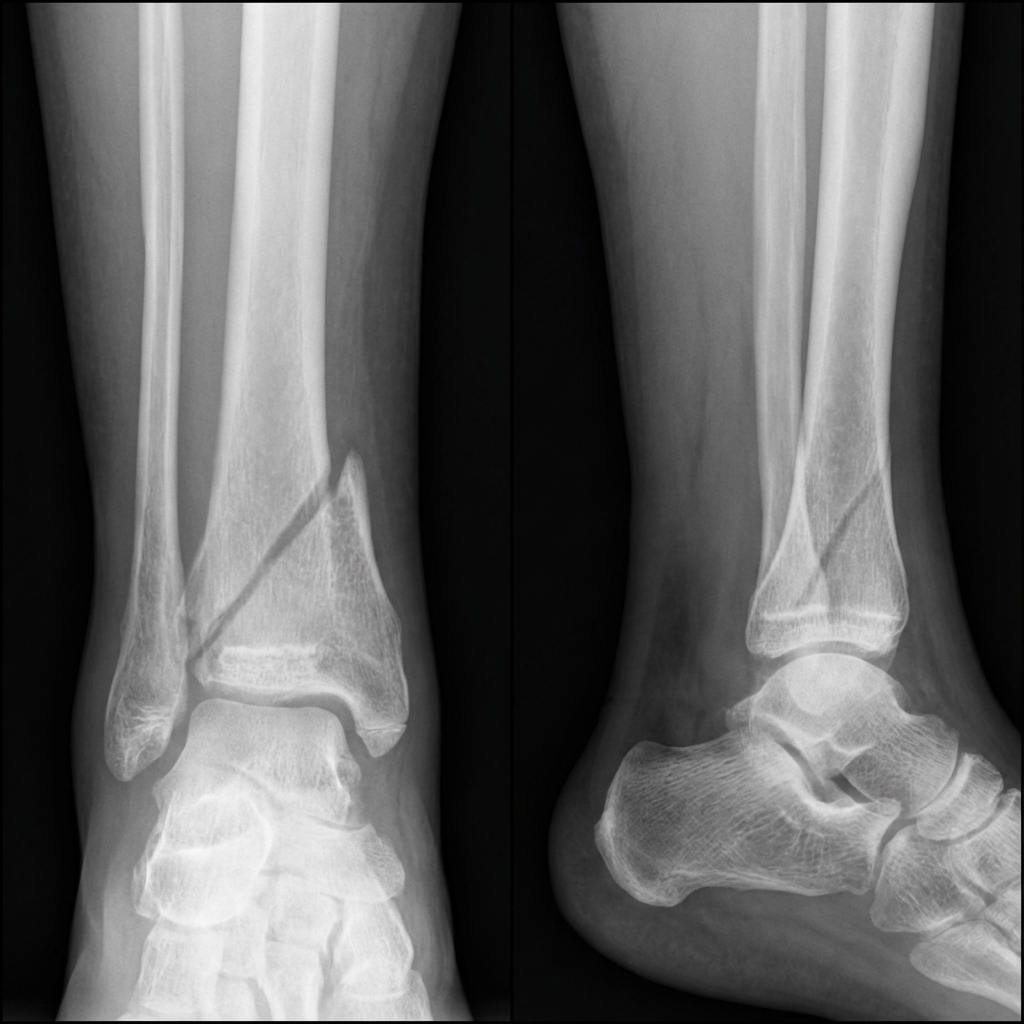

AP and lateral ankle radiographs in a 12-year-old child demonstrating a Salter-Harris Type II fracture of the distal tibia. The fracture line extends through the physis (S = separation) and exits through the metaphysis (A = above). A Thurston-Holland fragment is visible on the lateral side. The fibula is intact. The distal tibial physis is widened medially. This injury pattern is at risk for premature physeal closure.

Source: AI-Generated: Educational Radiograph of Salter-Harris Type II Fracture • OrthoVellum AI • OrthoVellum Educational Use